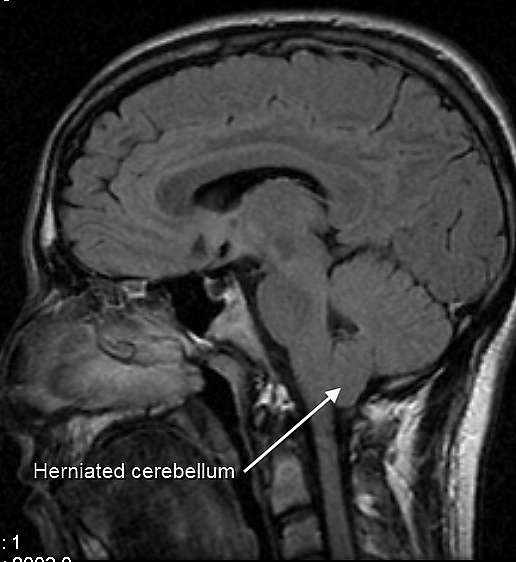

Синдром Арнольда — Киари (Q07.0 согласно МКБ-10[38]) включает в себя 4 типа заболеваний, обозначаемых соответственно синдром Арнольд-Киари I, II, III и IV[46].

Синдром Арнольда — Киари I — опущение миндалин мозжечка более чем на 5 мм за пределы большого затылочного отверстия в позвоночный канал[46].

Синдром Арнольда — Киари II — опущение в позвоночный канал структур мозжечка и ствола мозга, миеломенингоцеле и гидроцефалия[46].